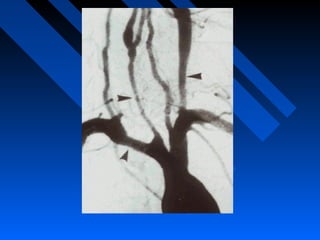

Giant Cell Arteritis

(Temporal arteritis)

• Occurring primarily over the age of 50

years.

• Frequent features include fatigue,

temporal headaches, jaw claudication,

loss of vision, scalp tenderness,

polymyalgia rheumatica and aortic arch

syndrome.

• Rarely involves the skin, kidneys and

lungs.

Temporal arteritis